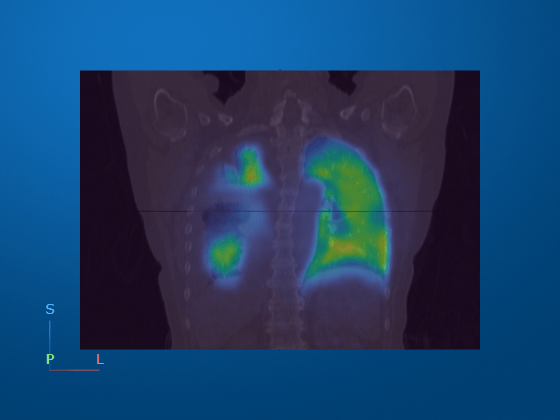

A PET and CT scan fusion image illustrating medical image processing with color-coded regions.

You can load and display multimodal medical images from PET and CT using Medical Imaging Toolbox. (See MATLAB documentation.)